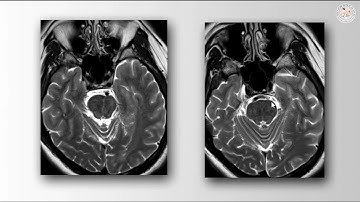

Vascular Loop decompression for trigeminal neuralgia